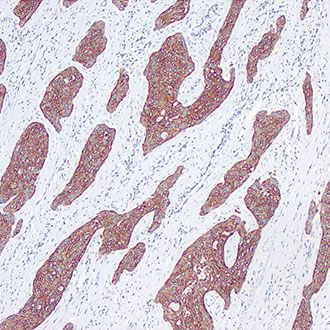

CK Pan

CK Pan -